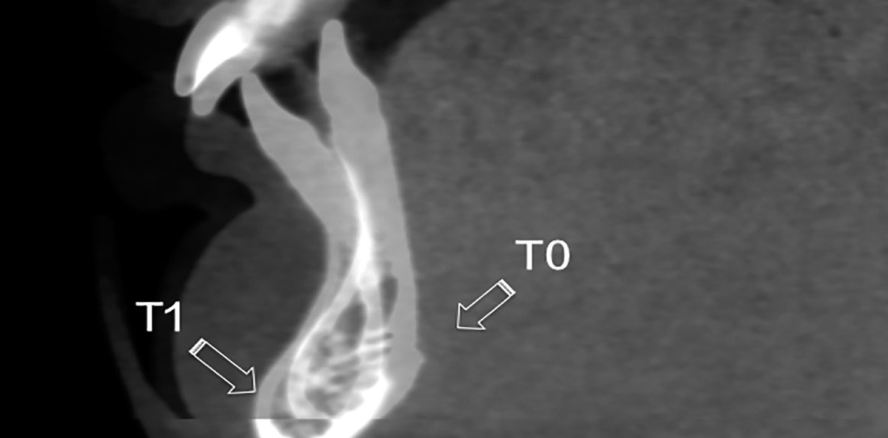

Fünfzig skelettale Klasse II-Patienten mit der Indikation einer mandibulären Vorverlagerung waren Gegenstand einer retrospektiven 3D-Untersuchung. Alle Patienten (zwischen 12 und 16 Jahren alt) befanden sich in der pubertären Phase (CS3 oder CS4). Aus ihren DVT-Aufnahmen wurden mithilfe einer Open-Source-Software (ref) virtuelle 3D-Modelle erstellt. Die Modelle wurden bei Anwendung einer an anderer Stelle beschriebenen Methodik1 in den Zielbereichen volumetrisch überlagert. Die Überlagerung der anterioren Schädelbasis wurde dabei für die Analyse der fazialen Gesamtveränderungen, der Unterkieferverlagerung sowie des Umbaus der Fossa glenoidalis verwendet. Die regionale Überlagerung wurde verwendet, um die Veränderungen im Ober- und Unterkiefer zu prüfen. Fünfundzwanzig Personen wurden mit der Herbst-Apparatur (HAG) bei voller Aktivierung in einem Schritt behandelt; die anderen 25 Personen, welche lediglich andere dentale Behandlungen erhielten (z. B. kieferorthopädisches Alignment und Nivellierung in Vorbereitung einer Herbst-Therapie, Zysten-Marsupialisation, Behandlung verlagerter bleibender Zähne), wurden als  Vergleichsgruppe (CG) hinzugezogen. Bei allen Patienten wurden zu zwei Zeitpunkten DVT-Aufnahmen erstellt – zu Therapiebeginn (T0) und nach der Behandlung (T1), wobei die Scans in einem Intervall von acht bis zehn Monaten gemacht wurden, je nach Bedarf. Die qualitative Bewertung mithilfe von semitransparenten Überlagerungen und farbcodierten Karten sowie die quantitative Bewertung mittels Punkt-zu-Punkt-Messungen erbrachten die folgenden Ergebnisse.

Der Knochenumbau fand bei den Herbst-Patienten auf der Artikulationsoberfläche der Fossa glenoidalis statt (ca. 0,5 mm; Abb. 4a, b), während in der Kontrollgruppe (CG) keine signifikante Veränderung gemessen werden konnte (Abb. 4c, d).